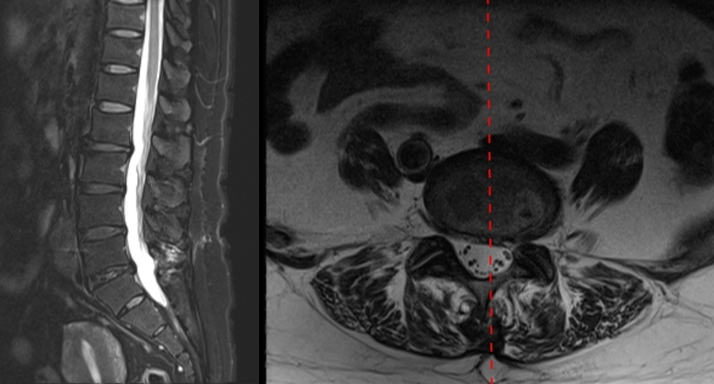

九、类脊髓高压综合征

病例

女,51岁。

主诉:腰疼伴左下肢疼痛麻木4个月。

既往史:椎间孔镜下椎间盘切除术(L4-5)。

术前

术中:术中硬膜破裂,灌洗液压力30mmHg,硬膜破裂后1小时出现血压升高,心率加快,手术持续2小时。

术后:延迟苏醒,拔管困难,转ICU,6小时候拔管神志恢复正常。

术后

思考与建议:

警惕硬膜损伤

全麻下早期表现:血压升高,心率加快

尽快结束手术或中转开放手术

有条件情况下给予硬膜修补

多数患者预后良好